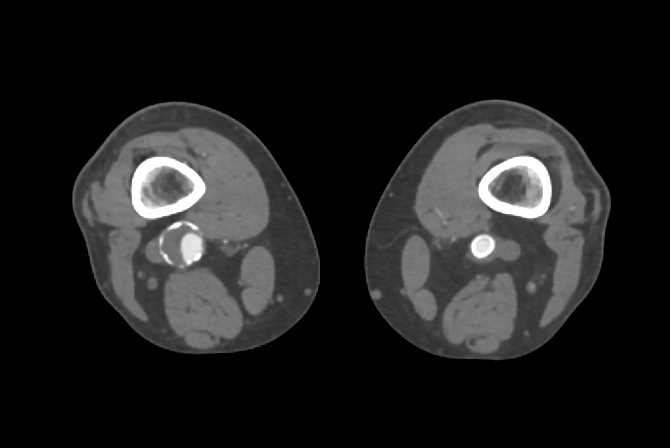

Two Renal Arteries to the Left Kidney